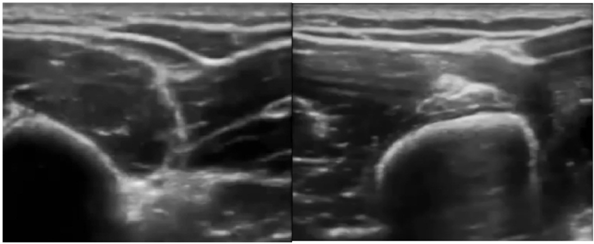

• Example of surgery at the distribution of lateral cutaneous nerve of the forearm and sonoanatomy as well as nerve block.